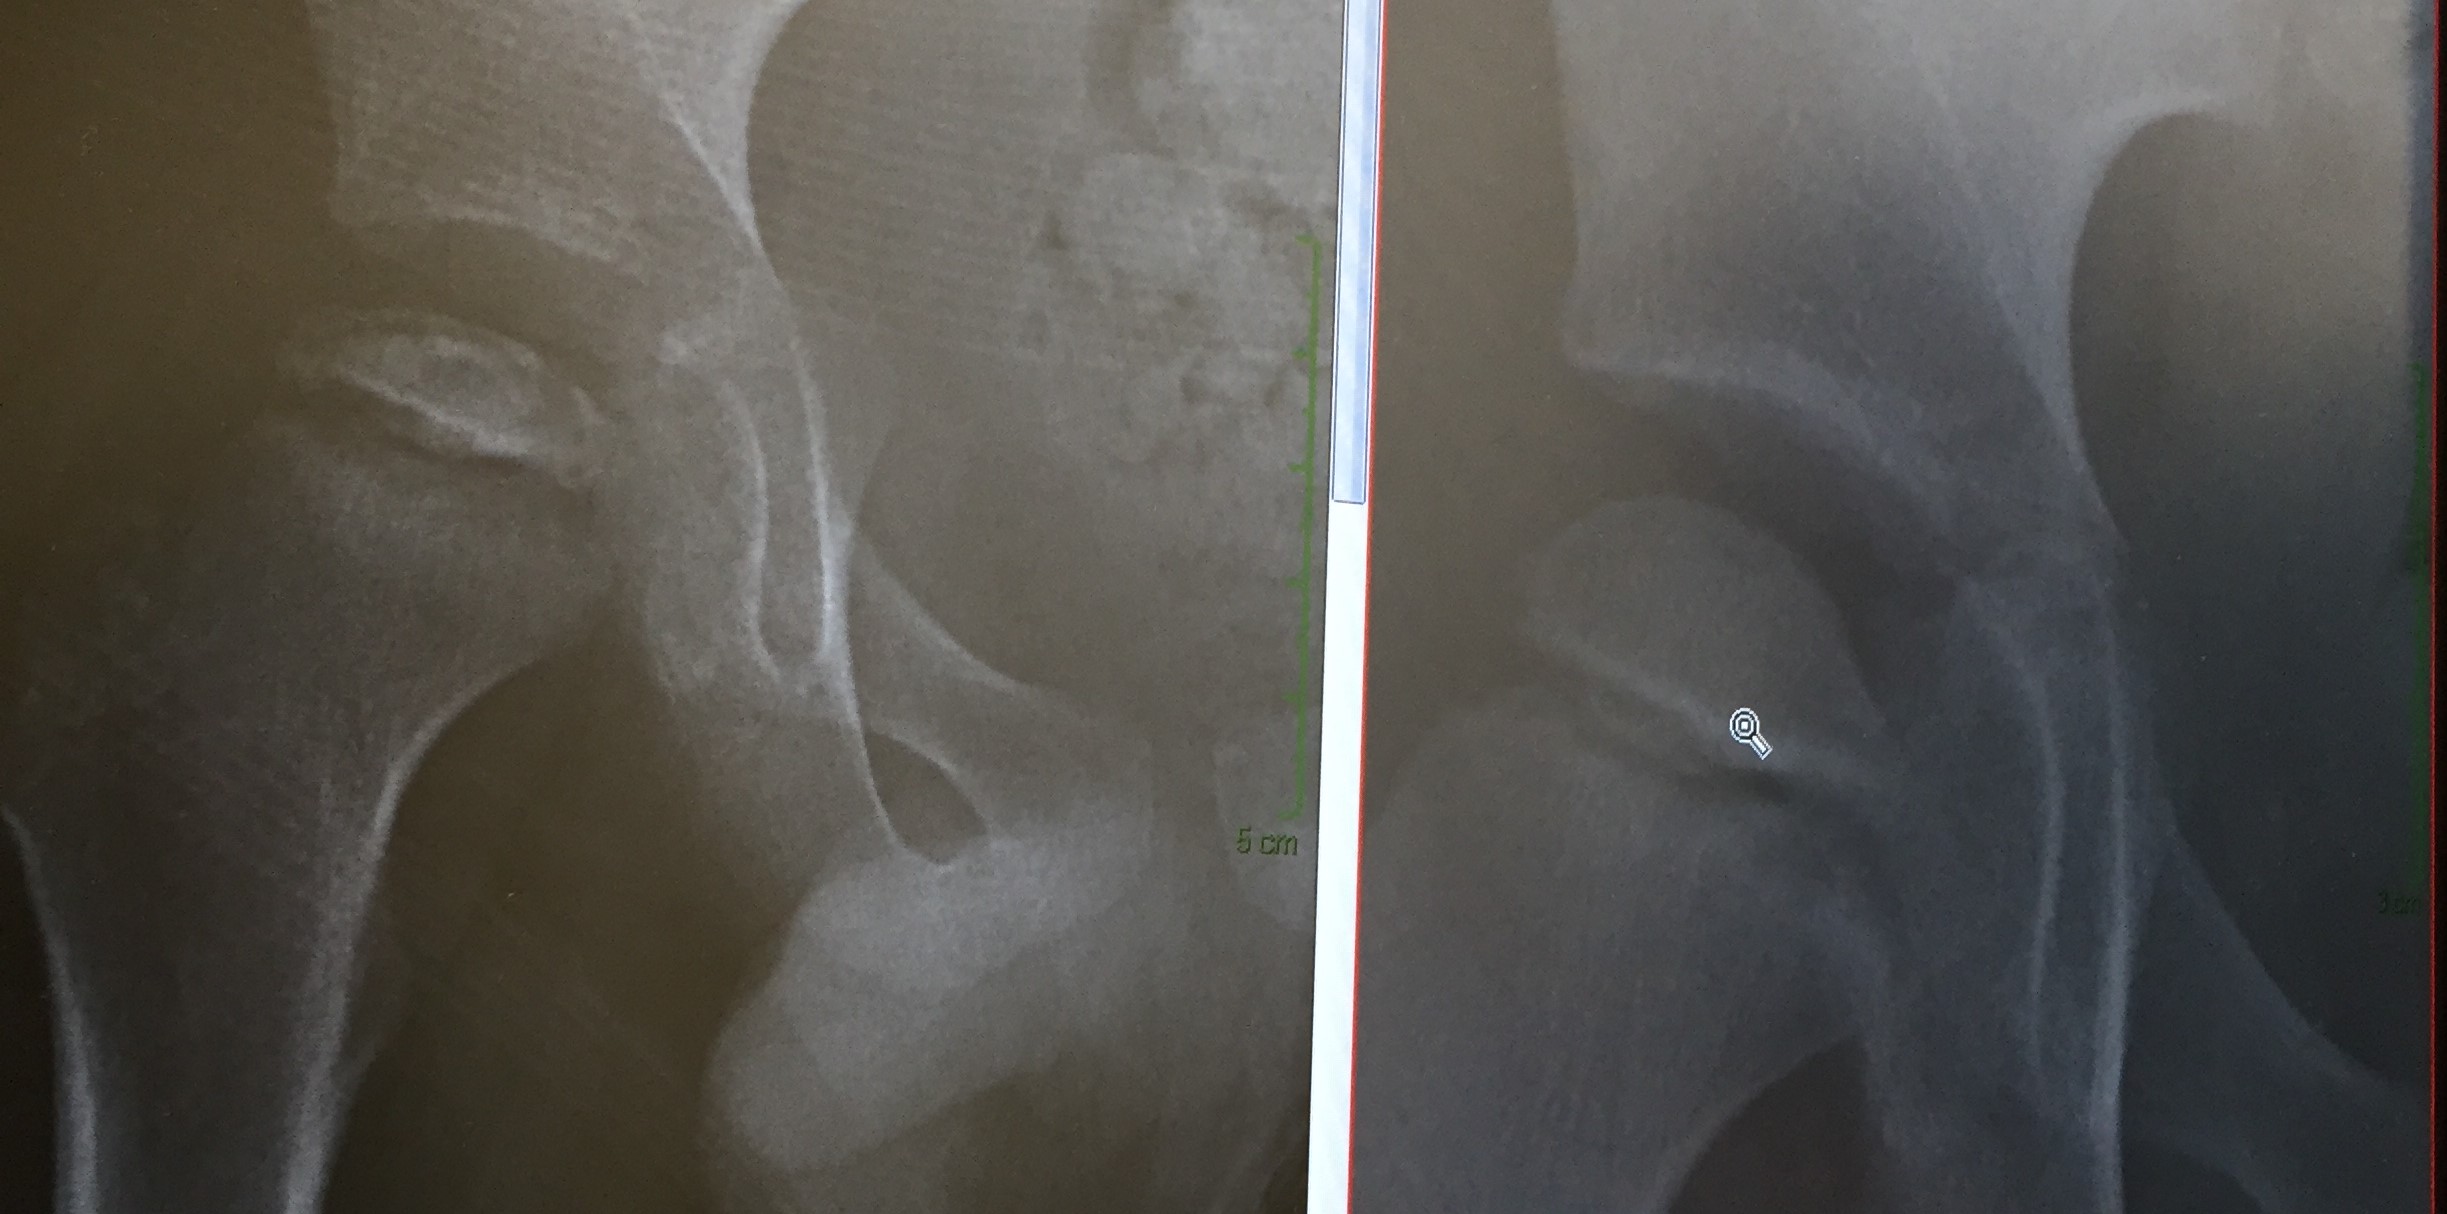

NovScan2

X-ray image

From denial to acceptance